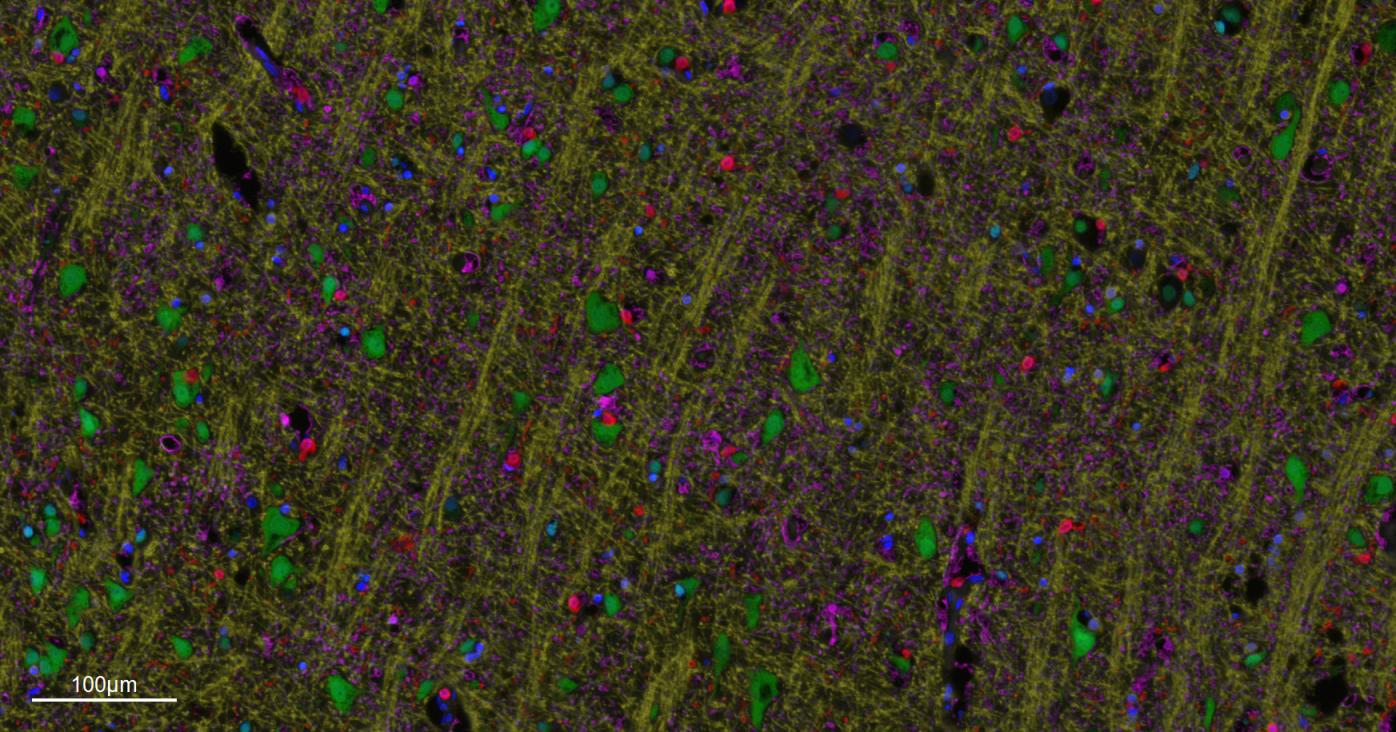

| IF | Human, Mouse, Rat | 1:200-1000 |